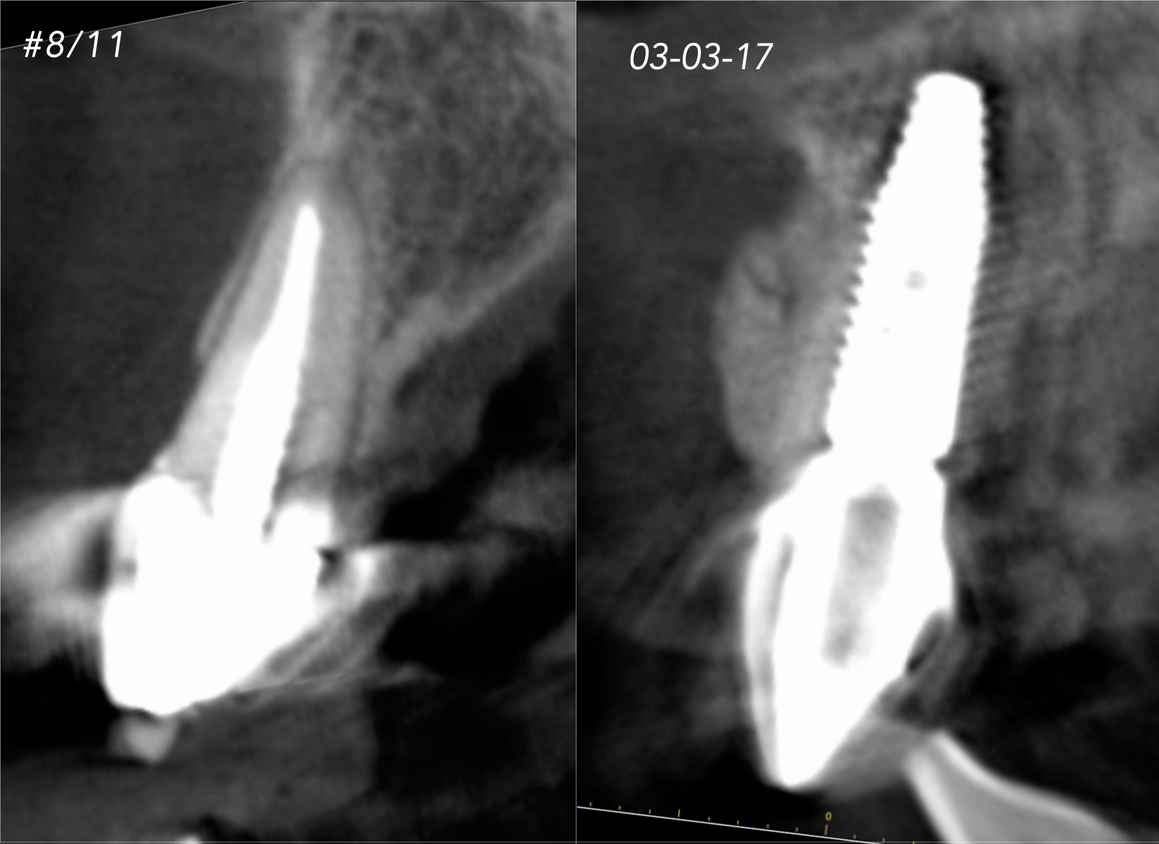

Clinical Cases CASE 1. COMPLEX IATROGENIC DEFECT CASE 2. CONGENITALLY MISSING LATERAL INCISORS CASE 3. VERTICAL AUGMENTATION CASE 4. VERTICAL AUGMENTATION CASE 5. IMPLANT BONE DEHISCENCE CASE 6. IMPLANT BONE DEHISCENCE CASE 7. KNIFE-EDGE RIDGE CASE 8. IMMEDIATE IMPLANT AND SIMULTANEOUS S.M.A.R.T.® HORIZONTAL AUGMENTATION CASE 9. IMMEDIATE IMPLANT AND SIMULTANEOUS S.M.A.R.T.® HORIZONTAL AUGMENTATION